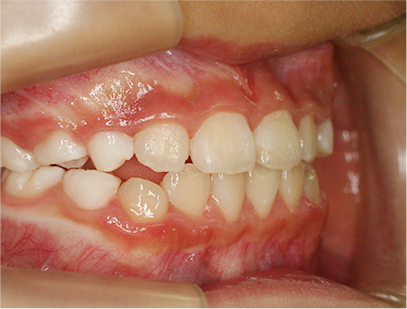

前歯部の開咬とデコボコ

前歯部が咬んでいないことを主訴として来院されました。精査、診断の結果「前歯部にデコボコを伴う開咬」と診断されました。

下の歯の裏側に舌が出ないように矯正装置を取り付け、そして上の歯には取り外しのできる矯正装置を装着して、側方に拡大を行います。

取り外しのできる矯正装置、舌が出せなくなる矯正装置(フェンス)